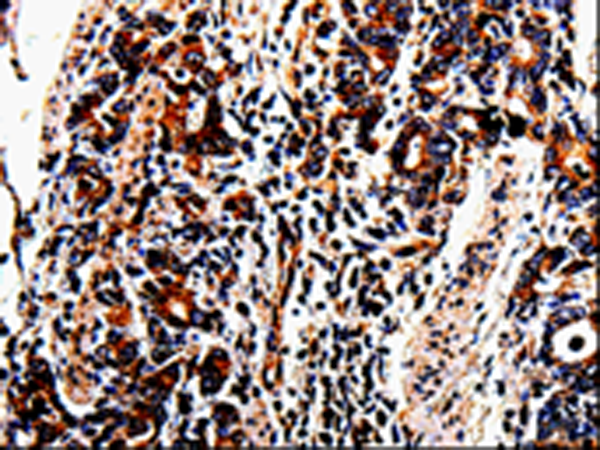

分类: 科研抗体货号: P06957别名: RAGE应用: WB,IHC反应种属: Human